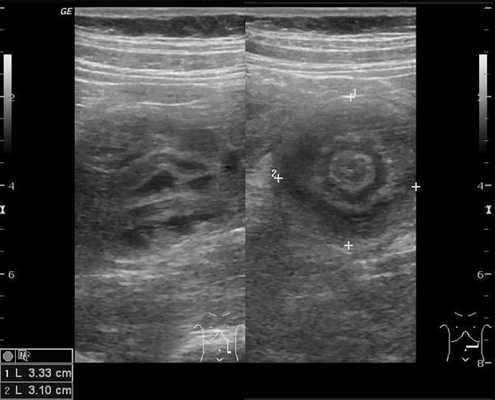

Золотым стандартом считается проведение ультразвукового исследования (сонографии) органов брюшной полости, так как оно является неинвазивным, быстрым, безопасным, безболезненным и высоко информативным методом. [9] [10] При помощи сонографии можно диагностировать инвагинат не только на типичных, но и на атипичных участках кишечника, что повышает точность установления и верификации диагноза.

В момент УЗ-исследования врач может определить один из симптомов:

- симптом мишени (за счёт внедрения одной кишки в другую инвагинат на срезе выглядит как мишень);

- симптом "почки с завоздушенным центром".